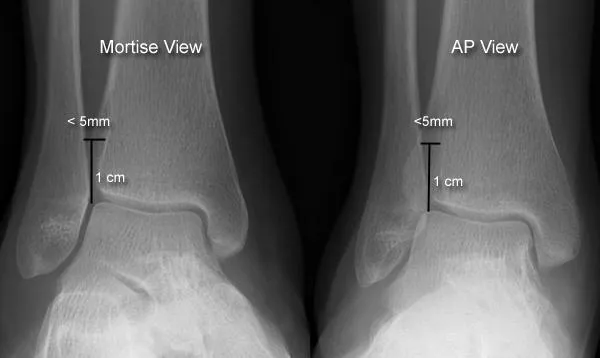

- X-rays: AP, Lateral, Mortise (for syndesmosis; medial clear space, tibiofibular overlap).

⭐ The mortise view X-ray is crucial for assessing ankle joint congruity; a medial clear space >4mm suggests deltoid ligament injury and instability.